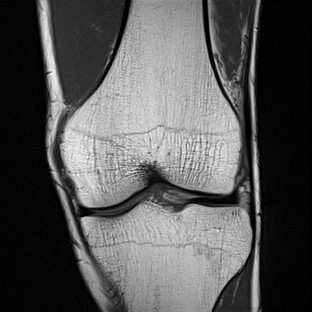

Limited by imaging systems, the reconstruction of Magnetic Resonance Imaging (MRI) images from partial measurement is essential to medical imaging research. Benefiting from the diverse and complementary information of multi-contrast MR images in different imaging modalities, multi-contrast Super-Resolution (SR) reconstruction is promising to yield SR images with higher quality. In the medical scenario, to fully visualize the lesion, radiologists are accustomed to zooming the MR images at arbitrary scales rather than using a fixed scale, as used by most MRI SR methods. In addition, existing multi-contrast MRI SR methods often require a fixed resolution for the reference image, which makes acquiring reference images difficult and imposes limitations on arbitrary scale SR tasks. To address these issues, we proposed an implicit neural representations based dual-arbitrary multi-contrast MRI super-resolution method, called Dual-ArbNet. First, we decouple the resolution of the target and reference images by a feature encoder, enabling the network to input target and reference images at arbitrary scales. Then, an implicit fusion decoder fuses the multi-contrast features and uses an Implicit Decoding Function~(IDF) to obtain the final MRI SR results. Furthermore, we introduce a curriculum learning strategy to train our network, which improves the generalization and performance of our Dual-ArbNet. Extensive experiments in two public MRI datasets demonstrate that our method outperforms state-of-the-art approaches under different scale factors and has great potential in clinical practice.